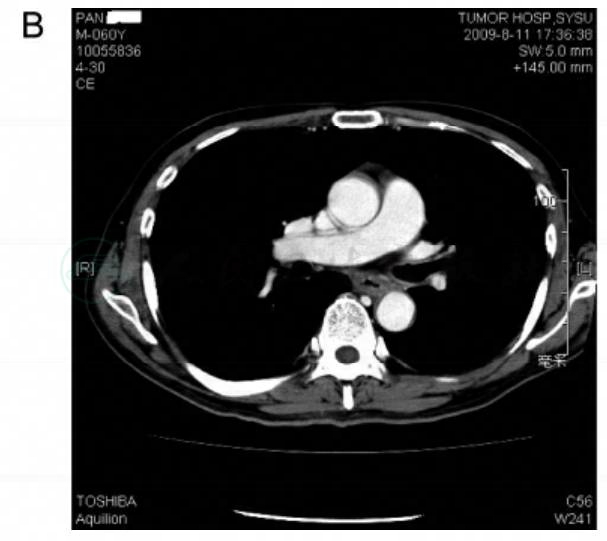

分期治疗是实体肿瘤治疗的基本原则之一,也是实体肿瘤治疗的基本条件和前提。食管超声内镜是目前对食管癌进行T分期和N分期的最佳工具。超声胃镜发现肿物与胸主动脉分界不清,提示肿瘤侵犯降主动脉的可能性极大(图3A)。增强CT扫描也提示肿瘤与降主动脉关系密切,怀疑累及降主动脉。按照2009年AJCC食管癌分期,应归于T4b病变。另外,超声胃镜发现食管周围的淋巴结均为长条形的小淋巴结,均值,界清;腹腔干和腹膜后等腹部区域也未发现肿大淋巴结。以上影像学特点提示患者的N分期应为N0。因为肿瘤上缘靠近气管隆突,为进一步评估肿瘤与双侧支气管以及隆突的关系,入院后行电子纤维支气管镜检查。支气管镜下见隆突锐利,双侧支气管通畅,无外压表现,支气管黏膜光滑,提示隆突及支气管受侵的可能性不大。颈部、胸部、腹部平扫及增强CT均未发现食管外的可疑转移灶,提示M分期应为M0。

图3 放化疗前胸部增强CT扫描提示肿瘤与降主动脉关系密切(A);放化疗后胸部增强CT扫描提示肿瘤明显缩小(B)

放化疗后疗效评价:食管超声內镜发现距门齿30cm处食管黏膜见一约1.0cm×1.0cm糜烂面,表面充血(图1B);距门齿30~35cm处食管左侧壁全层低回声增厚,最厚约7.4mm,与胸主动脉分界尚清(图2B)。CT提示病灶较前明显缩小(图3B)。食管吞钡示放化疗后病灶已不明显(图4B)。综上所述,放化疗后影像学疗效评价为PR,遂按计划给予手术治疗。